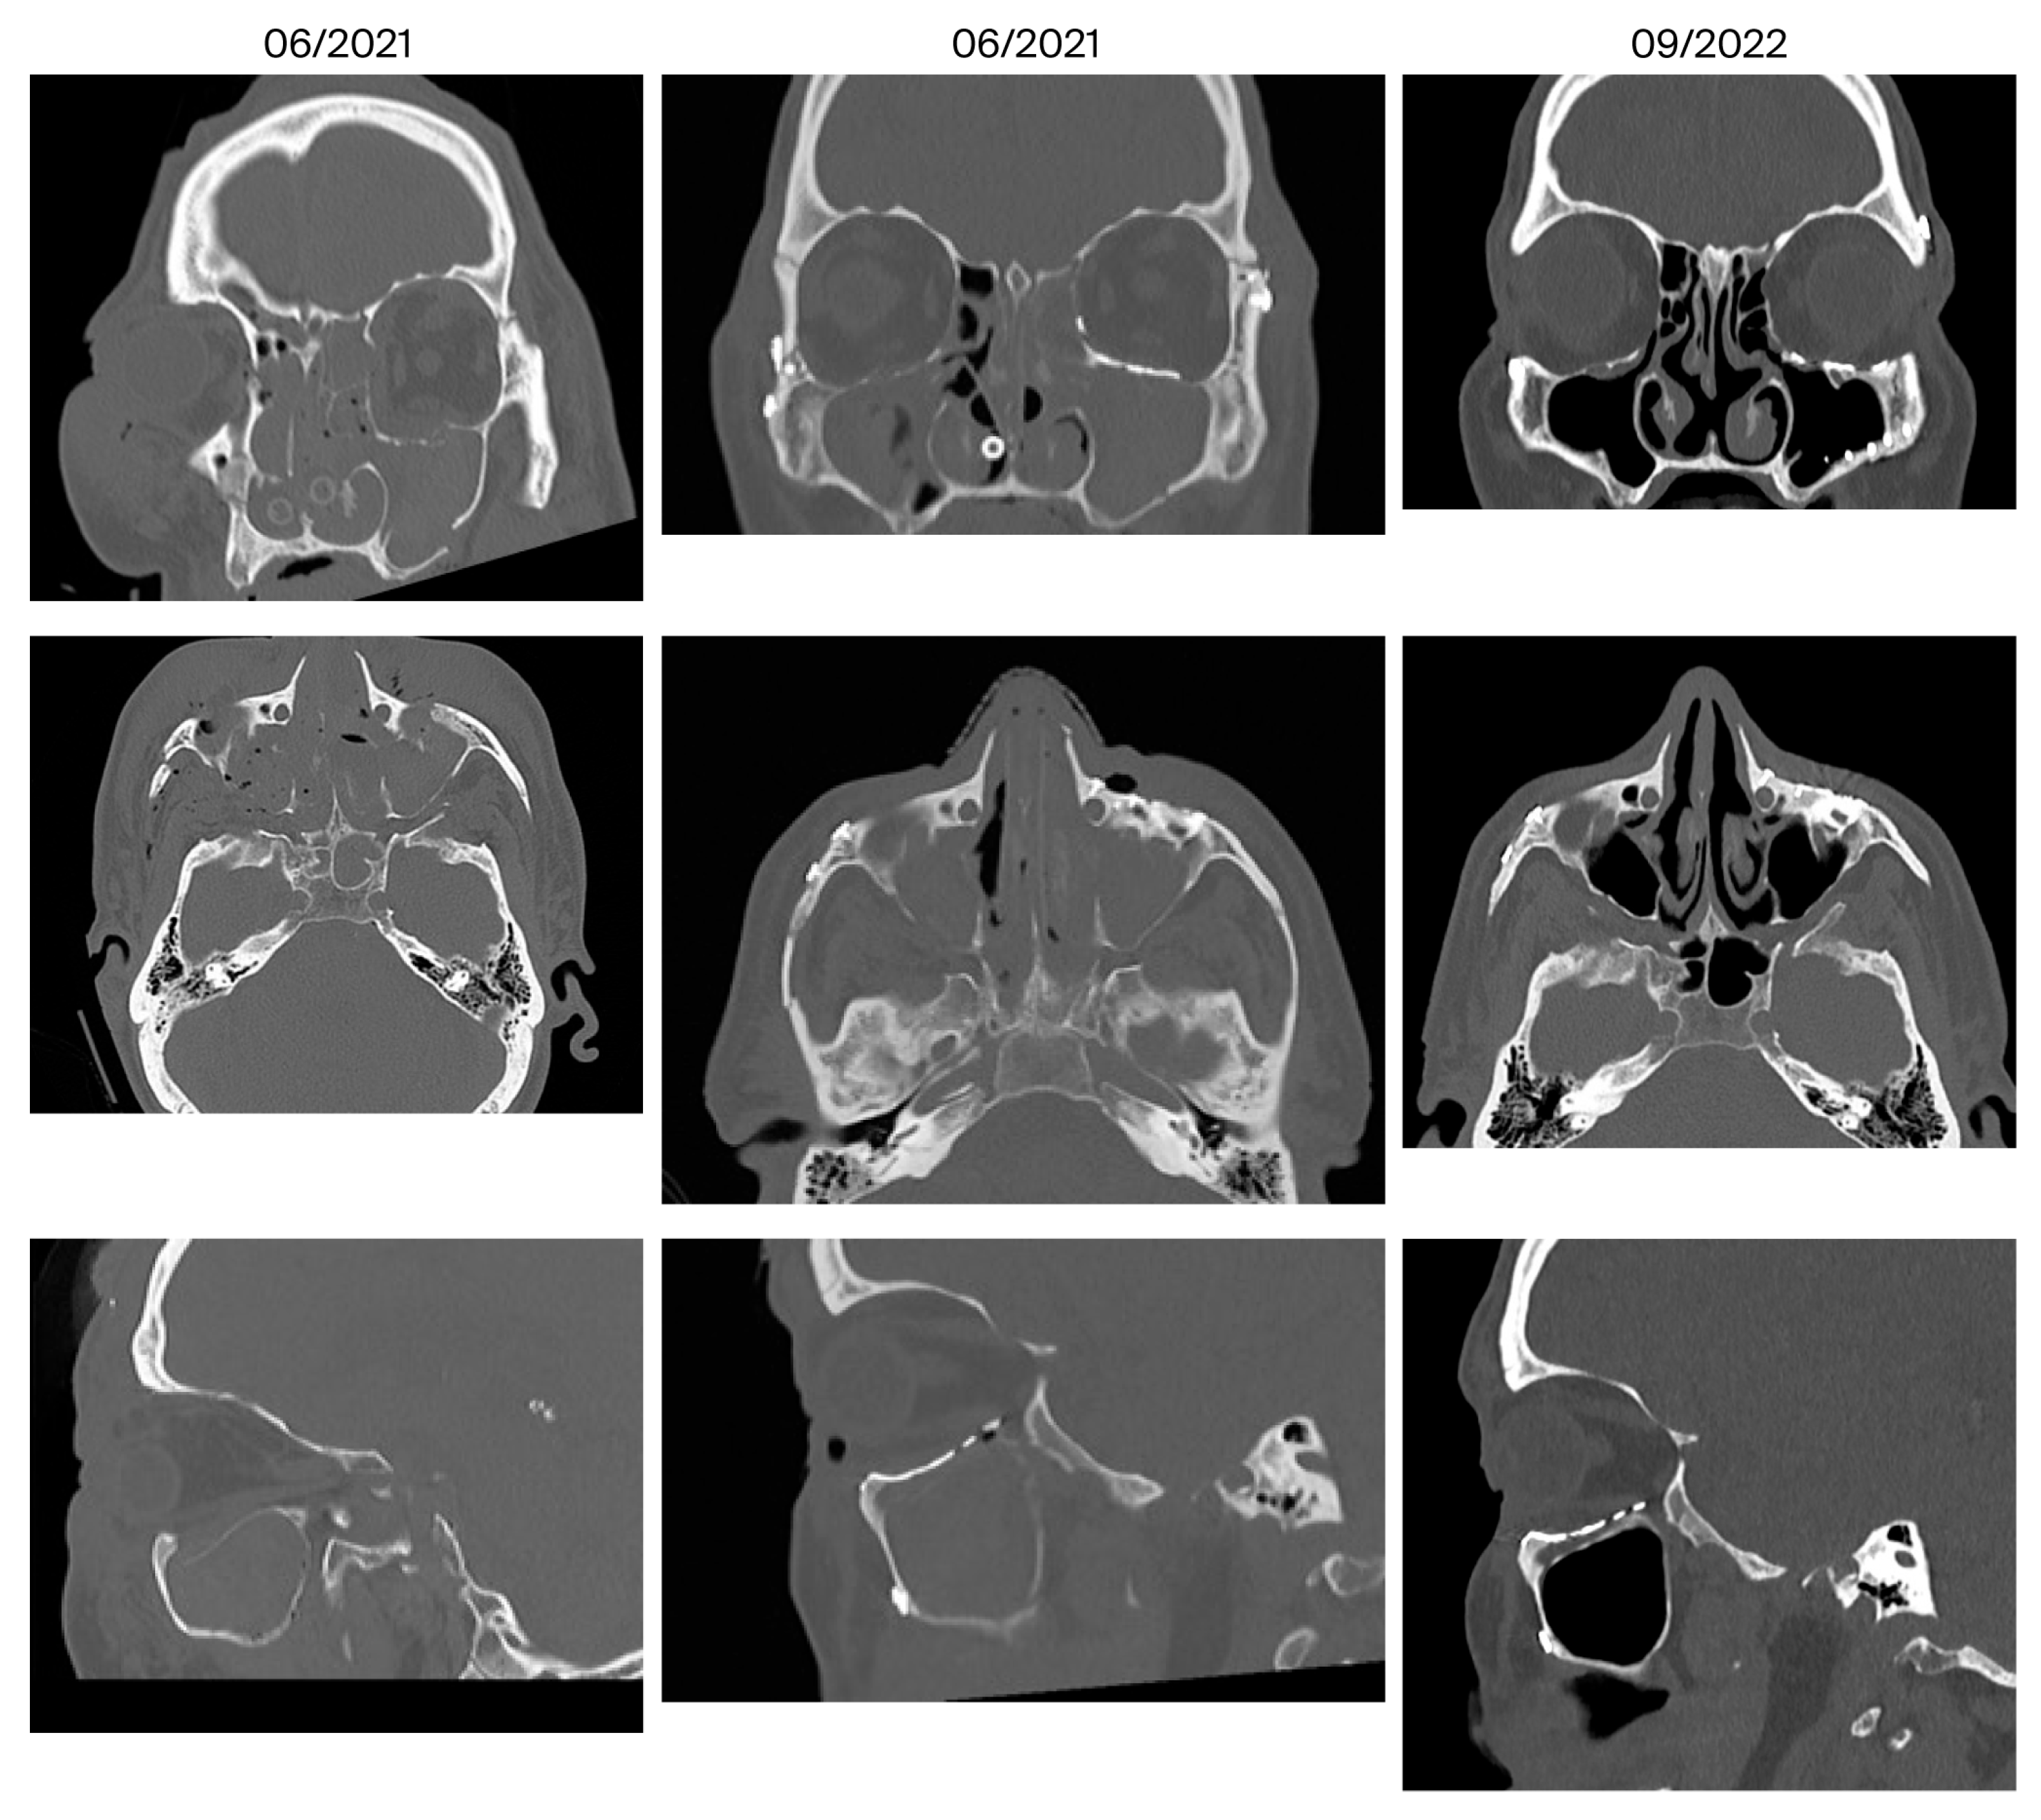

- Bone apposition at the PSI as a sign of osseointegration (n = 16)

- Remodeling of the dislocated bone fragments of the orbital walls (n = 16), including in the area of the infraorbital canal.

4.3. Remodeling